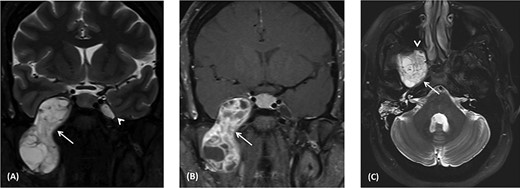

(A) Coronal T2 MRI shows dumbbell-shaped soft tissue mass with heterogenous high signal intensity across the widened oval foramen extending from the infratemporal fossa into Meckel’s cave (arrow). It displaces the temporal lobe superiorly and laterally. The left Meckel’s cave (arrowhead) is normal. (B) Coronal post-contrast T1 MRI shows heterogeneous enhancement of the right dumbbell mass across the right oval foramen (arrowhead). It shows multiple necrotic foci. (C) Axial T2 MRI shows heterogeneous high signal intensity mass at the level of foramen ovale abutting the petrous segment of the right internal carotid artery with no invasion (arrow). Anteriorly, the mass indents the posterior wall of the right maxillary antrum (arrowhead). Right mastoid air cells opacification secondary to obstructed right Eustachian tube.

A magnetic resonance imaging (MRI) scan revealed a large dumbbell-shaped mass extending across the right skull base with intracranial and infratemporal fossa components in the path of the trigeminal nerve (Fig. 1A). It extends intracranially into the anteromedial aspect of the middle fossa into right Meckel’s cave with compression of the adjacent right cavernous sinus. The adjacent temporal lobe shows displacement laterally but no infiltration. Post-contrast images show heterogenous enhancement with solid and necrotic components (Fig. 1B). The posterior aspect of the skull base component of the mass abuts the horizontal segment of the right internal carotid artery along the carotid canal but without invasion (Fig. 1C). It compresses the right Eustachian tube with resultant opacification of the right mastoid air cells. The anterior aspect of the mass abuts the posterior wall of the right maxillary antrum. The overall appearance is likely representing schwannoma of the mandibular branch of the right trigeminal nerve.